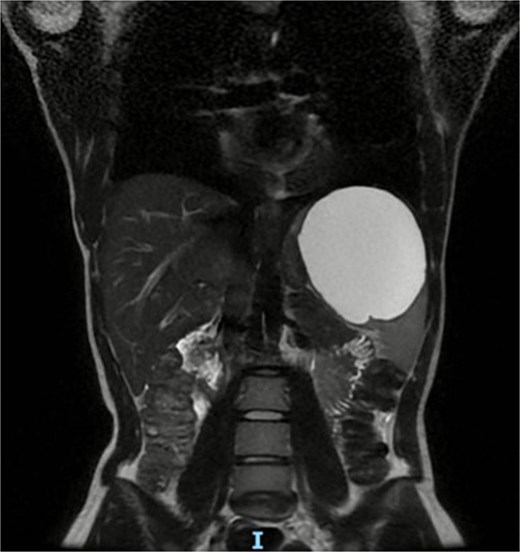

We present a 22-year-old female patient with no relevant past medical history who, 6 months prior to diagnosis, began experiencing mild abdominal pain and distension in the upper abdomen. Laboratory studies showed a white blood cell count of 9500/μl, lymphocytosis of 19%, and neutrophilia of 74.1%. Magnetic resonance imaging reported a giant splenic cyst, ~13 cm (Figs 1 and 2).

Axial view or preoperative MRI of splenic cyst, diameter of 13 cm.